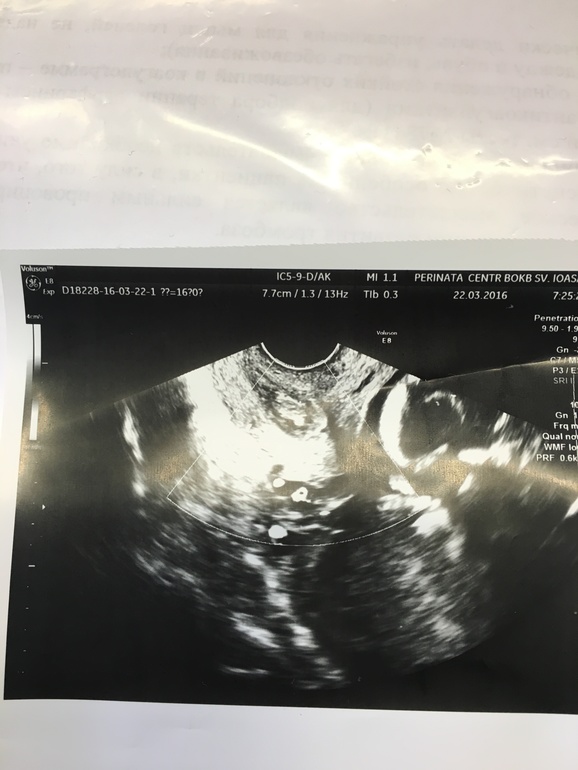

Кому ошибались с полом в 16 недель?

Пол малышамы с мужем очень ждали парня,сегодня на узи показали девочку.Врач говорит прям чётко писюшку видно.На след узи через 3 недели,вдруг ещё чето вырастет)))))